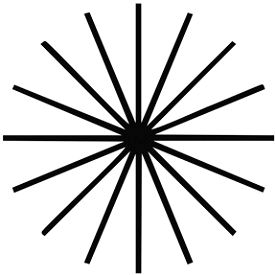

Закрийте одне око, зробіть 3-5 кроків назад від монітора і подивіться на круг. Зверніть увагу, не стають чи деякі з ліній темніше, ніж інші. Якщо так, можливо у вас астигматизм.